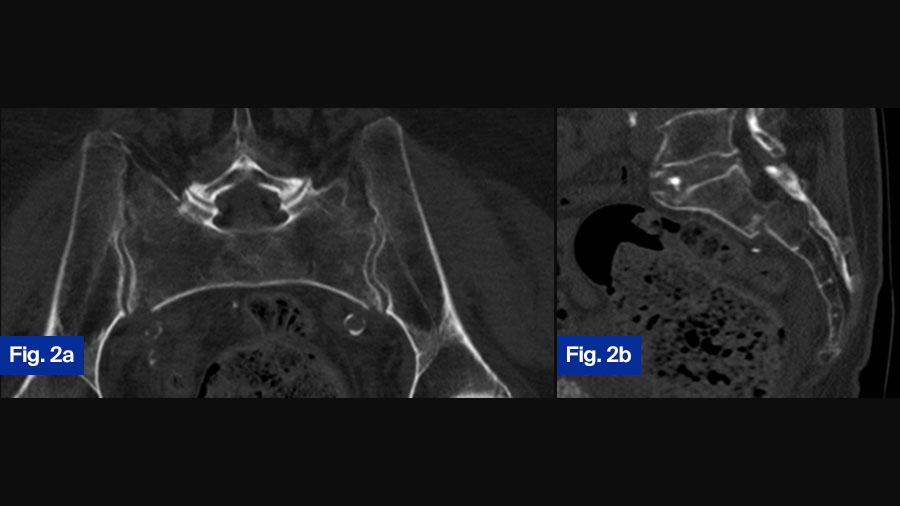

Case Study 2: 92-year-old female with bilateral sacral fracture (FFP Type IVb)

Figure 2. 92-year-old female patient presenting 1 week after fall from standing height with immobilizing pain at lower lumbar spine. (a) Axial CT demonstrating slight displacement of bilateral sacral fracture; (b) sagittal CT with displaced transversal fracture at S1/S2 level. The fracture was classified as FFP type IVb. (c) Lateral fluoroscopic image orientated in direction of the patient (bottom anterior, left cranial) showing overlapping of ilio-cortical densities and ischial notch.

The drill guide is placed centrally in S1 corridor caudal to the ilio-cortical densities. (d) Oblique obturator view to assess the abutment of the washer on the iliac cortex.

Postoperative control at discharge, patient is mobile with a walker ( (e) anterior–posterior, (f) inlet, and (g) outlet view ).